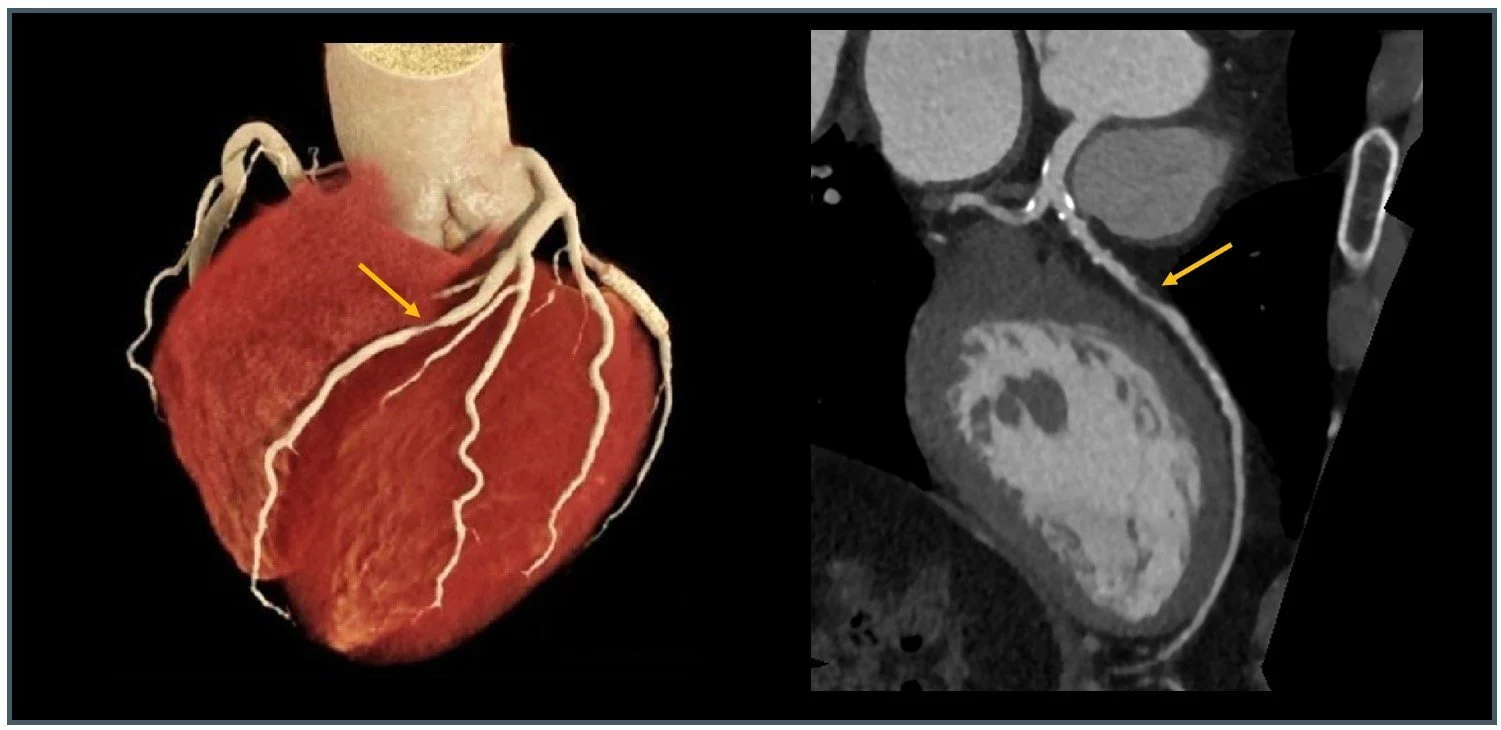

CT Coronary Angiogram (CTCA)

CT coronary angiography (CTCA) is a non-invasive medical imaging technique used to visualise the coronary arteries that supply blood to the heart muscle. Detailed three-dimensional images of the coronary arteries can be generated, assisting in the diagnosis of coronary artery disease, blockages, or other structural abnormalities. The valuable information obtained by CT coronary angiography plays a crucial role in supporting Cardiologists clinical decisions for treatment planning and patient management.